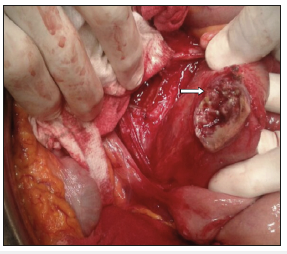

Deshpande et al were the first to describe an endovascular repair of an SAEF in a high-risk patient.6 The advantages of the endovascular approach are the rapid control of hemorrhaging and the avoidance of an intervention in a hostile abdomen or the avoidance of a procedure in patients with severe comorbidities unfit for open surgery. On contrary, the endovascular approach has great limitations as the bowel defect is not repaired; thus, infection, if present, may persist, and retroperitoneum debridement is not feasible. Recent review study on outcomes after the endovascular repair of SAEF by Kakkos et al showed that the endovascular approach was associated with a high incidence of persistent, or recurrent infection, or recurrent bleeding that significantly limited survival rates. Prognosis were worse in patients with perioperative sepsis, large bowel fistulization, and no intestinal repair. Bergqvist and Björck also reported that preoperative evidence of sepsis was an indicating factor for unfavorable outcomes. So endovascular management of the SAEF without further aortic reconstruction, followed by isolation of the eroded part of the duodenum and therapy, can be considered as a potentially effective treatment. Postoperatively, the patient should be treated with intravenous broad-spectrum antibiotics for up to 6 weeks according to the culture results (Figures 7 & 8).

Figure 7:External view of the affected jejunum loop after en bloq resection of the aneurysmatic aortic defect was carried out.

Figure 8:Prisssmary suture of the jejunal defect (A). The aneurysmatic aortic defect still remains opened in the picture, showing the intern fistulous orifice (B)./p>